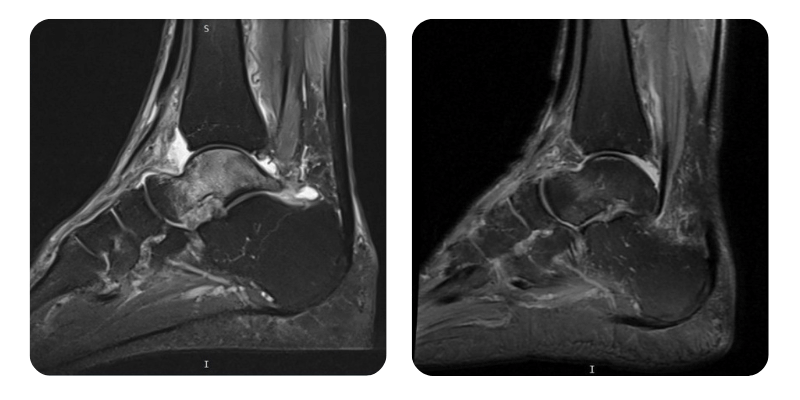

Előtte

Utána

T.F., 68 éves – Jobb oldali talus avaszkuláris nekrózisa

Anamnézis: Három hónappal ezelőtt a páciensnek jobb oldali distalis peroneus epiphysis törése volt, amelyet gipszrögzítéssel kezeltek. Egy hónappal később bokaficam következett be, amelyhez fájdalom társult. Az MRI-vizsgálat asepticus talus nekrózist igazolt. A beteg ismert hipertóniás, Preductallal kezelve, valamint prosztata adenomája is van.

Diagnózis: Jobb oldali talus avaszkuláris nekrózisa.

Terápiás beavatkozások: 20 alkalom hiperbár oxigénterápia.

Lefolyás: Az ödéma körülbelül 90%-ban eltűnt.